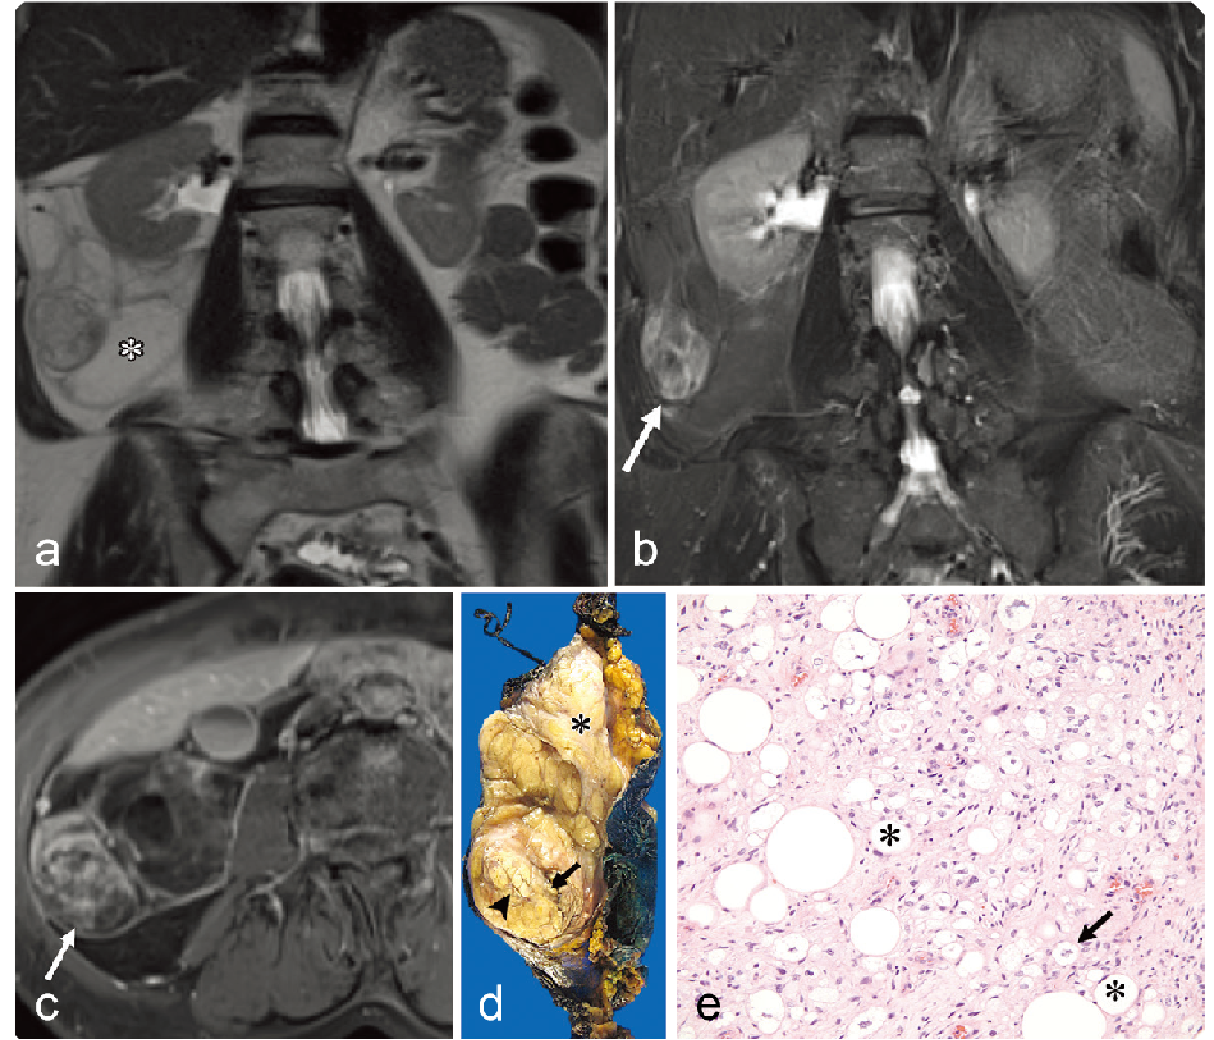

59b3732e0785f667336ea7dc317ef2cc.png

病例 3:粘液型脂肪肉瘤  68岁男性,腹痛3个月,逐渐加重

(a, b) T2WI (a) 和T2WI-FS (b)显示盆腔肿瘤呈高信号(*),内可见花边状低信号(箭)。(c) 对比增强 T1WI-fs显示肿瘤内斑片状强化区(箭)。(d) 大体病理显示双瓣状、边界清楚的肿块,切面呈棕黄色、凝胶状,光滑闪亮(*),另见占总表面积30% 的出血区域(**),肿瘤似乎完全被薄的纤维假包膜(箭)包裹。(e) 低倍镜显示丰富的粘液样基质,其中包含纺锤形肿瘤细胞和网状的毛细血管系统(箭)(HE×100)。